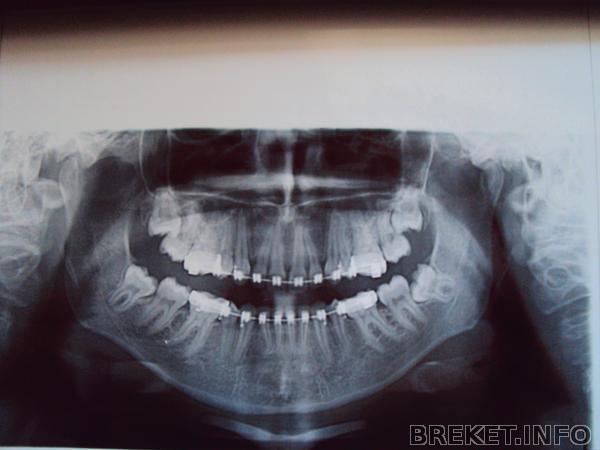

Пришла я значит с повторным снимком к своей ортофеечке, а она смотрит, решает где чего подтянуть и говорит страшнейшее из моих ожиданий: Ну что, 8-ки то будем удалять? я говорю: а что надо? я думала она имела ввиду удаление тех восьмерок которые в десне лежат а оказывается она про те которые сверху ровно стоят и удалять их не потому что мешают а потому что я их плоховато прочищаю. Я сказала что теперь буду стараться и она вроде как согласилась, потому что она сказала чистить лучше. Ух. Потом мне одели железную лигатуру на ВЧ (проволочку тоненькую) еще плюс и чейн поменяли и на НЧ и на ВЧ. Читать далее »

dsc00573.jpg

Ребята,как считаете стоит ли удалять восьмерки из десны?какова вероятность,что когда они решат вылезти,остальные зубы сдвинуться?